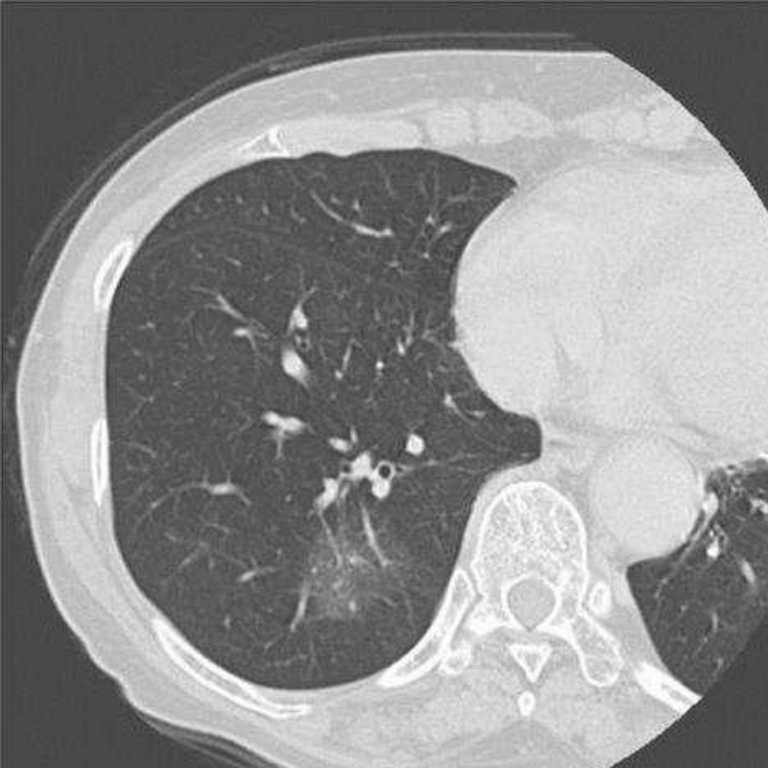

由於低劑量輻射胸部電腦斷層可以偵測到0.2公分大小的病灶,然而並非所有的肺結節都是惡性腫瘤,也可能是肺部感染留下的疤痕或纖維化等良性組織。這些微小的肺結節在診斷預後上造成困難,因此醫師常會建議以電腦斷層追蹤,追蹤之間隔則需視肺結節的大小、質地、形狀、有無鈣化而定。

肺結節的質地可分為純毛玻璃狀、部分實質性、完全實質性。純毛玻璃狀病灶很有可能是原位肺腺癌或是癌症前期病灶-非典型腺瘤增生。

若肺結節為純毛玻璃狀且大於0.8公分,或是為部分/完全實質性,則會建議手術切除;若小於0.8公分的純毛玻璃狀病灶,則建議3個月後再追蹤電腦斷層,2次追蹤後病灶若無縮小情況,則考慮手術。若小於0.5公分的純毛玻璃狀病灶,則半年後再追蹤電腦斷層,無明顯變化再拉長追蹤期間。若追蹤期間出現實質化之變化,則建議手術切除。

A.純毛玻璃狀肺結節